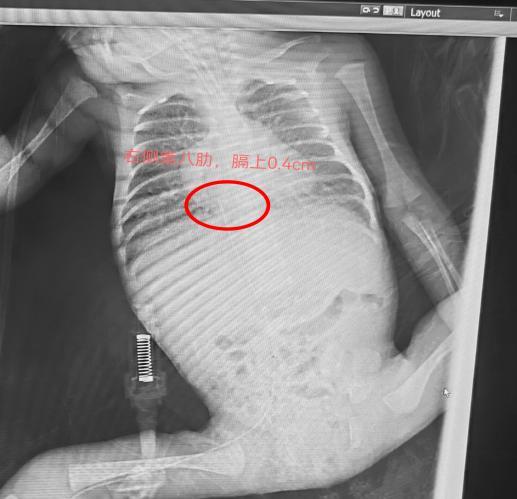

助手新生儿科副护士长蔡明明备好置管物品,在为宝宝做好保暖的前提下摆好体位,林海珊护士长以24G留置针做引导,选择右下肢的小隐静脉进针,“一针见血”,根据赛丁格操作步骤,缓慢的将导管送入到血管内,导管回血通畅,最后经床旁 X 线确定了 PICC 导管尖端的位置良好,为宝宝建立了一条生命的“静脉通路”。24G留置针是当前国内留置针规格最小的,套管直径仅0.72mm,比常规使用的20G留置针管径小0.38mm,整个过程中出血量极少。该早产儿在赛丁格技术下成功完成穿刺。